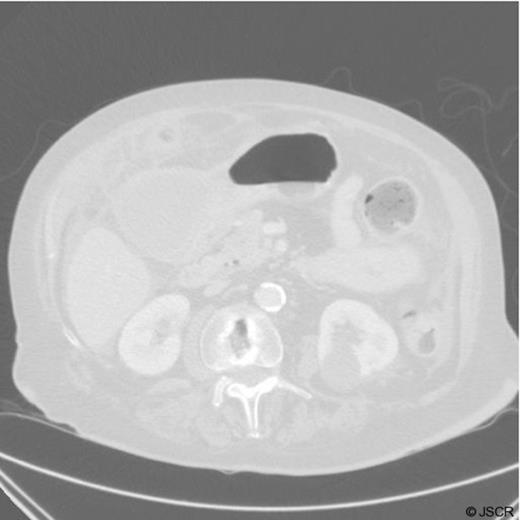

The pathology report confirmed that the gallbladder had features of chronic cholecystitis and the gastric mucosa was consistent with a duplication cyst that did not communicate with the gastric cavity. There was no evidence of dysplasia or malignancy.

Histological specimen demonstrating the cyst overlying the stomach

Specimen demonstrating a gastric duplication cyst in the gastric lining